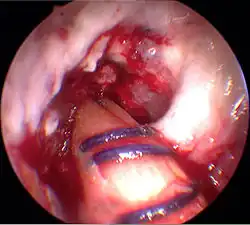

L'endobouton est tiré avec le transplant à travers le trou par le fil de traction, et ensuite fixé en tirant sur le fil de bascule.

Le transplant est obtenu par une section médiane sur le tibia, juste au-dessous du genou, au moyen d'un tendon stripper (décolleur de tendon), d'un ring stripper (décolleur en rond) ou encore d'un harvester (récolteur). Selon la longueur, le prélèvement sur le tendon est mis en triple ou en quadruple avec une certaine technique de couture, arrangé, noué et conduit par un trou dans le tibia jusqu'au fémur, où il est fixé de même. Depuis le début du XXIe siècle, on dispose d'une technique peu invasive pour le prélèvement plus facile et rapide sur le tendon au creux du genou, avec de meilleurs résultats cosmétiques[219].

La technique opératoire la plus moderne est la technique du double faisceau (double bundle technique). Au moyen de quatre canaux dans l'os, deux faisceaux de tendons (antéromédial et postérolatéral) sont fixés dans le genou. Par une meilleure imitation de l'anatomie, les résultats produits sont plus stables. Par ailleurs ce procédé est techniquement plus exigeant, et n'est utilisé actuellement (2010) que dans quelques centres spécialisés. La fixation des deux transplants a lieu exclusivement hors de l'articulation par des endoboutons[220].

Enfilage du transplant

Le transplant est inséré au moyen de deux fils de traction du bas vers le haut dans les trous percés. Au moyen d'une vis creuse, le transplant est fixé au fémur. L'extrémité sortant du canal du tibia est pré-tendue et fixée par coincement avec une vis d'interférence (vis delta). Puis les orifices opératoires sont recousus, en laissant un drain aspiratif. La durée de l'opération est environ de 45 à 90 min.